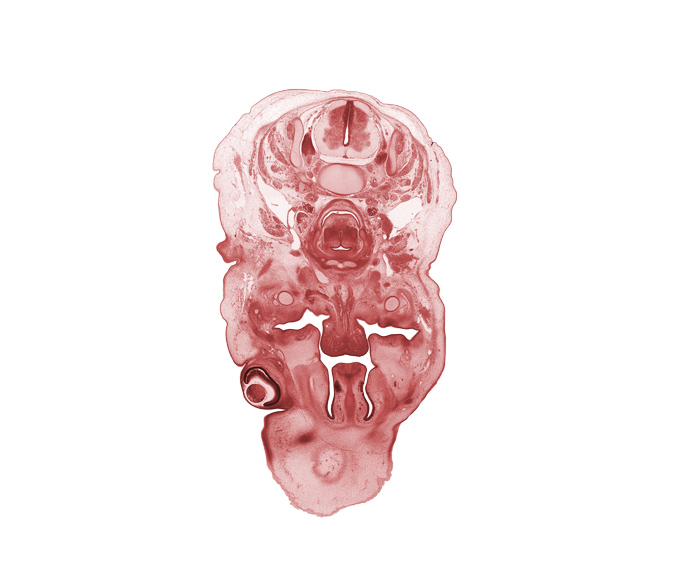

C-4 spinal ganglion, C-5 spinal ganglion, arytenoid condensation, body of hyoid (pharyngeal arch 3 cartilage), choana, edge of subarachnoid space, hypoglossal nerve (CN XII), inferior pharyngeal constrictor muscle, laryngeal inlet, laryngeal pharynx, longus cervicis muscle, nasal cavity (nasal sac), oral cavity, palatine shelf, retropharyngeal space, sympathetic trunk, vomeronasal organ

Carnegie Embryo #462   |   Location: 5-03-05

Keywords: C-4 spinal ganglion, C-5 spinal ganglion, arytenoid condensation, body of hyoid (pharyngeal arch 3 cartilage), choana, edge of subarachnoid space, hypoglossal nerve (CN XII), inferior pharyngeal constrictor muscle, laryngeal inlet, laryngeal pharynx, longus cervicis muscle, nasal cavity (nasal sac), oral cavity, palatine shelf, retropharyngeal space, sympathetic trunk, vomeronasal organ